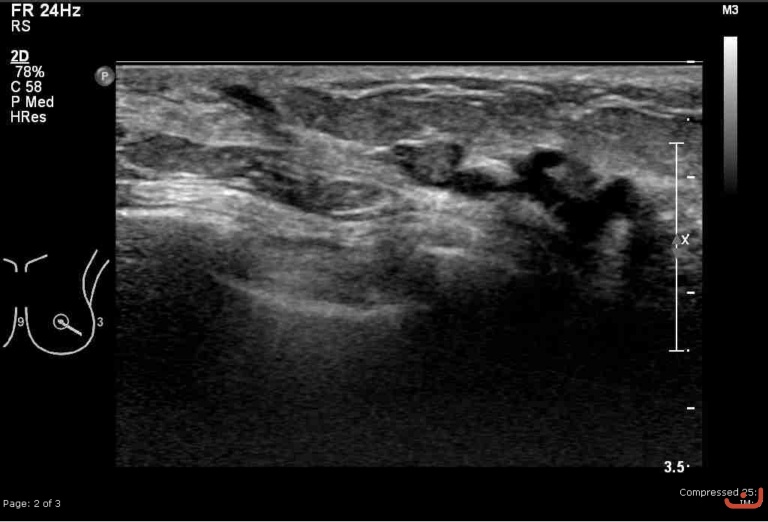

Malignant solid mass

Thursday, 30 April 2015